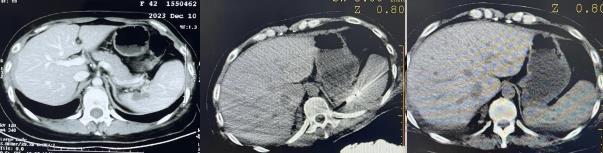

2023年,也就是王女士术后六年,在一次随诊中她再次被发现新病灶,结合各项检查结果考虑病情复发且情况较为复杂。出于对医院医疗实力和服务的认可,王女士选择再次来到哈医大肿瘤医院进行治疗。

接诊后,消化内科的陶冀教授团队立即结合病史及辅助检查结果多方讨论,反复推敲王女士的诊疗经过和病情变化,对病情进行综合研判。团队经多次分析,认为这次复发的病灶尽管波及多个部位,难度较大,但微波消融手术在治疗肿瘤和其他局部病变方面,具有明显的优势,团队最终决定为王女士实施脾脏转移结节微创消融手术。

由于脾脏特别容易出血,此次手术具有很强挑战性,为此团队制定了针对性手术方案。手术在全麻下进行,成功穿刺并准确置入病灶,多循环消融,直至完全覆盖病灶。手术采用中高功率消融,精准操作,所以过程中无明显出血和气胸。术后,王女士病情稳定,很快再次回归了家庭、社会。